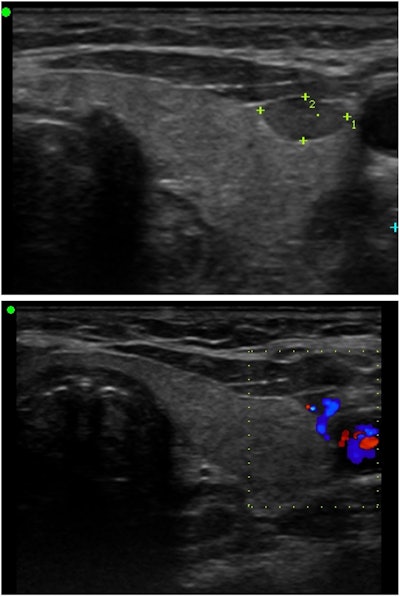

Parathyroid surgeons may choose to become proficient at neck ultrasonography as studies show an advantage to surgeon performed ultrasound with high sensitivity and specificity.2 Sestamibi (planar) scanning utilizes the tendency of parathyroid glands to concentrate 99mTc-sestamibi to localize abnormal glands. Single photon emission computed tomography (SPECT) produces 3D images and can be fused with a low CT to create SPECT/CT studies. Combined with delayed imaging, these have a high degree of sensitivity and specificity for parathyroid localization. Sestamibi imaging performed immediately preoperatively also allows for the use of radiolocalization intraoperatively. Limitations of this imaging modality include small glands, patients with multigland disease, and variability in quality and availability of SPECT/CT between institutions. Contrast enhanced CT has been increasingly utilized in parathyroid localization and is often referred to as four dimensional CT (4D-CT). In its simplest form, this uses non-contrast images and arterial phase contrast enhanced images to identify parathyroid adenomas. On non-contrast images, a parathyroid adenoma should appear hypodense relative to the thyroid gland. The parathyroid adenoma should avidly enhance on arterial phase contrast images (Figure 2). If a venous washout phase is included, parathyroid adenomas should have early venous washout relative to the thyroid and lymph nodes. 4D-CT is especially useful in re-operative parathyroid surgery and is good for identifying deep superior parathyroid adenomas that may not be visible on ultrasound. It has been shown to successfully identify small glands that may not be seen on other imaging modalities. Because of the contrast load, it should be avoided in patients with renal insufficiency.

Figure 2. Axial CT non-contrast (left) and arterial phase contrast (right) demonstrating left thyroid tubercle (+) and right superior parathyroid adenoma (*). The parathyroid adenoma is hypodense relative to the thyroid gland on the non-contrast image and avidly enhances on the arterial phase contrast image while the thyroid tubercle is isodense to the thyroid on the non-contrast image.Figure 2. Axial CT non-contrast (left) and arterial phase contrast (right) demonstrating left thyroid tubercle (+) and right superior parathyroid adenoma (*). The parathyroid adenoma is hypodense relative to the thyroid gland on the non-contrast image and avidly enhances on the arterial phase contrast image while the thyroid tubercle is isodense to the thyroid on the non-contrast image.